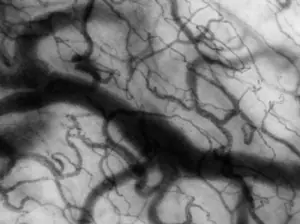

A microcirculação humana é um continente microscópico onde a vida se decide em escalas diminutas, mas com consequências imensas. É nesse território composto por arteríolas, capilares, vênulas e pelo delicado epitélio endotelial que o organismo negocia permanentemente o abastecimento de oxigênio, a remoção de resíduos metabólicos, o equilíbrio térmico, a vigilância imune e até a arquitetura da reparação tecidual. Embora represente apenas cerca de 7% do volume sanguíneo total, essa rede organiza-se em padrões fractais, como descreve Gutterman, replicando curvas, ramificações e proporções que garantem que nenhuma célula do corpo permaneça distante da fonte que a sustenta. É uma obra de engenharia viva onde a geometria serve à fisiologia e onde o acesso ao oxigênio — a moeda energética da existência — é minuciosamente orquestrado.

Essa complexa rede não funciona como um simples duto; ela pensa, interpreta e responde. Cada porção do microvaso é um espaço de tomada de decisão hemodinâmica. A arteríola terminal regula o fluxo com sensibilidade quase nervosa; o capilar, com seu revestimento unicelular, cria a superfície através da qual moléculas e sinais atravessam; as vênulas, por sua vez, acolhem, drenam e também sinalizam. O glicocálice endotelial paira sobre essa estrutura como um véu bioquímico vibrátil: é barreira, sensor, tradutor de forças de cisalhamento e estrutura antiflogística. Quando este delicado tapete de proteoglicanos e glicoproteínas se rompe, seja por inflamação, hiperglicemia ou trauma circulatório, a permeabilidade se altera, a adesão leucocitária aumenta e os alicerces silenciosos da homeostase começam a ruir — evidência clara de que a microcirculação é o primeiro lugar onde a doença se manifesta, muitas vezes antes que a macrocirculação denuncie qualquer alteração perceptível.

Mas é na entrega final do oxigênio ao tecido muscular que a microcirculação revela uma beleza quase dramática. Durante décadas imaginou-se um gradiente suave e progressivo entre o capilar e as mitocôndrias. Descobertas recentes, porém, mostram que esse percurso é marcado por quedas abruptas de pressão parcial de oxigênio, especialmente na finíssima distância que separa o eritrócito da membrana endotelial. Pesquisadores como Poole demonstram que este pequeno percurso — inferior a cinquenta micrômetros — é, paradoxalmente, o grande gargalo fisiológico do transporte de oxigênio. O oxigênio precisa atravessar membranas, dissolver-se brevemente no plasma, cruzar o glicocálice, penetrar o endotélio, alcançar o interstício, entrar na fibra muscular e, finalmente, alcançar as mitocôndrias, que hoje são compreendidas menos como organelas isoladas e mais como redes contínuas, de plasticidade dinâmica, capazes de transmitir energia e até facilitar o transporte molecular. Nesse cenário revisado, a microcirculação não é apenas condutora: ela é coautora da respiração celular.

Assim, a microcirculação humana não deve ser entendida como simples rede de tubos microscópicos, mas como uma ecologia viva, onde fluido, sinalização, metabolismo e estrutura se condensam em uma coreografia contínua. Através dela o organismo interpreta necessidades, antecipa riscos e molda respostas. É o teatro íntimo onde o oxigênio se converte em energia, onde a inflamação nasce ou se resolve, onde o movimento se inicia, onde a vida pulsa em escala imperceptível. Quem observa a microcirculação testemunha a própria lógica da fisiologia: um diálogo constante entre fluxo e forma, entre limite e adaptação, entre fragilidade e potência. É ali, no sopro das pequenas correntes, que o corpo negocia sua permanência no mundo.